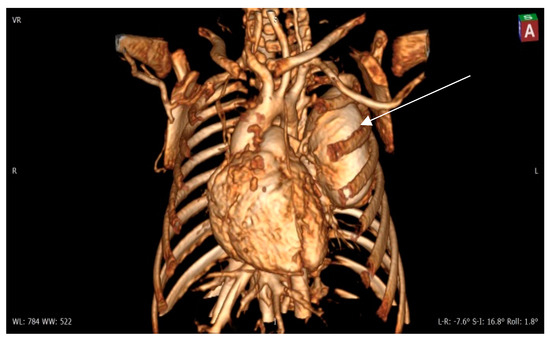

Figure 4. Contrast 3D-CT reconstruction of the structure in the left lung—arrow directed to the PAVM. A rounded formation is present in the left lung constituting the “external manifestation” of the arteriovenous fistula.